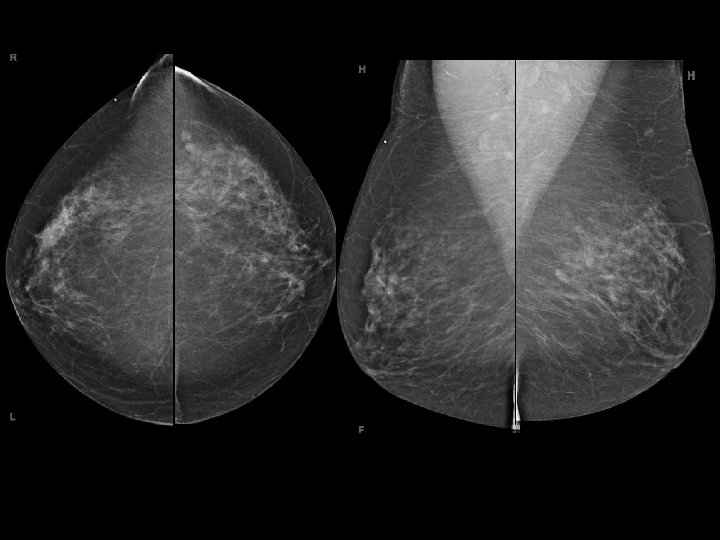

Proposed Solution Develop formula to better select patients for BCT � Tumor size/volume: : Breast size/volume � Density Limitations � Mammography compression � Some tumors easier to measure than others Mammographic Tumor density type � Discrepancy between imaging/pathology

Clinical Need Software/programming solution � Automate (or partially automate) breast and tumor volumes from a mammogram � Select ROI calculate � What we know… Breast thickness from compression Clear margins of breast tissue based on anatomy � Variables Tumor size may not be reproducible Density** Could use 2 D or 3 D (tomosynthesis)

Image Samples